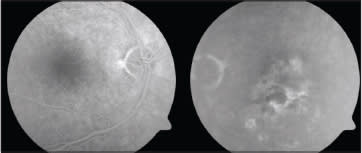

Fluorescein angiography of the right eye was unremarkable. Transit of the left eye showed blocking hypofluorescence corresponding to the subretinal hemorrhage with adjacent leakage hyperfluorescence consistent with choroidal neovascularization (Figure 2).

Figure 2. Late-phase fluorescein angiography revealing a normal transit in the right eye (5:56) and leaking hyperfluorescence, as well as blockage from subretinal hemorrhage, in the left eye (6:31).